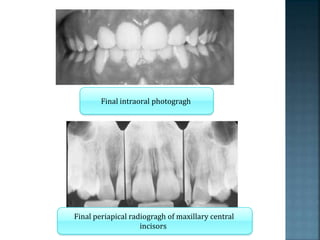

Final intraoral photogragh

Final periapical radiogragh of maxillary central

incisors

Final intraoral photogragh Finalperiapical radiogragh of maxillary central incisors